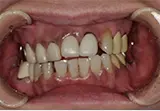

| 年齢/性別 | 50代女性 |

| 主訴 | 左下奥歯に痛みがある、全体的に治したい |

| 治療内容 | 全体的に歯周病やむし歯、根の治療を行い、仮歯を使用して咬合治療を実施。右下2本、左下1本の計3本を抜歯し、その後、右下に2本、左下に2本の計4本のインプラントを埋入しました。 |

| 治療期間 | 8か月 |

| 費用 | 2,106,500円税込 |

| リスク・副作用 | 炎症反応によって術後に腫れが生じることがあります。その程度は、手術の範囲や方法によって異なりますが、多くの場合、時間の経過とともに徐々に治まります。 ごく稀に、下顎奥歯の外科手術後に、唇や顎に痺れを感じることがあります。 |